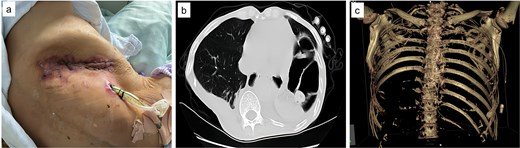

Upon admission, chest computed tomography (CT) and gastroscopy confirmed persistent esophagopleural fistula and empyema (Fig. 1a-c). A multidisciplinary team formulated a stepwise management plan: Stage 1: Under CT guidance, a chest drainage tube was reinserted. The nutrition team optimized nutritional status, correcting hypoalbuminemia and anemia. Thoracic drainage fluid culture revealed multidrug-resistant Pseudomonas aeruginosa; based on antimicrobial committee advice, local treatment (twice-daily 250-ml saline irrigation) was prioritized over systemic antibiotics. Stage 2: After 1 month, the drainage fluid became clearly transparent. However, CT showed unchanged fistula and cavity (Fig. 2a). Thus, a surgical plan was developed. CT-based three-dimensional reconstruction (Fig. 2b-d) guided surgery. Under general anesthesia, a 15-cm incision was made over the 10th rib. The latissimus dorsi muscle flap was dissected with preserved blood supply (Fig. 3a). Intercostal structures were preserved. The 9th and 10th ribs were transected 2 cm from the purulent cavity margin; the 11th and 12th ribs, 2 cm from the vertebral column. After thorough irrigation, a washable drainage tube was placed with its distal end toward the fistula. Muscle flaps were inserted into the cavity and sutured with antibacterial Vicryl (Fig. 3b and c). Finally, the incision was sutured (Fig. 3d). Stage 3: Skin depressions were compressed with cotton pads and a chest strap for 2 weeks (Fig. 4a). Sensitive antibiotics were administered for 2 weeks; intermittent saline irrigation-maintained drainage patency. The drain was removed at 3 weeks. Postoperative CT showed satisfactory recovery (Fig. 4b and c); the duodenal tube was removed 1 month later, and the patient resumed a normal diet gradually. As of July 2025, he remained symptom-free with no recurrence.

Post-admission chest CT and gastroscopy. (a) Mediastinal window showing esophageal fistula (arrow) and empyema (arrow); (b) lung window confirming the 67 × 36 × 117 mm right empyema; (c) gastroscopy identifying a 8 mm fistula (arrow) 38 cm from incisors.